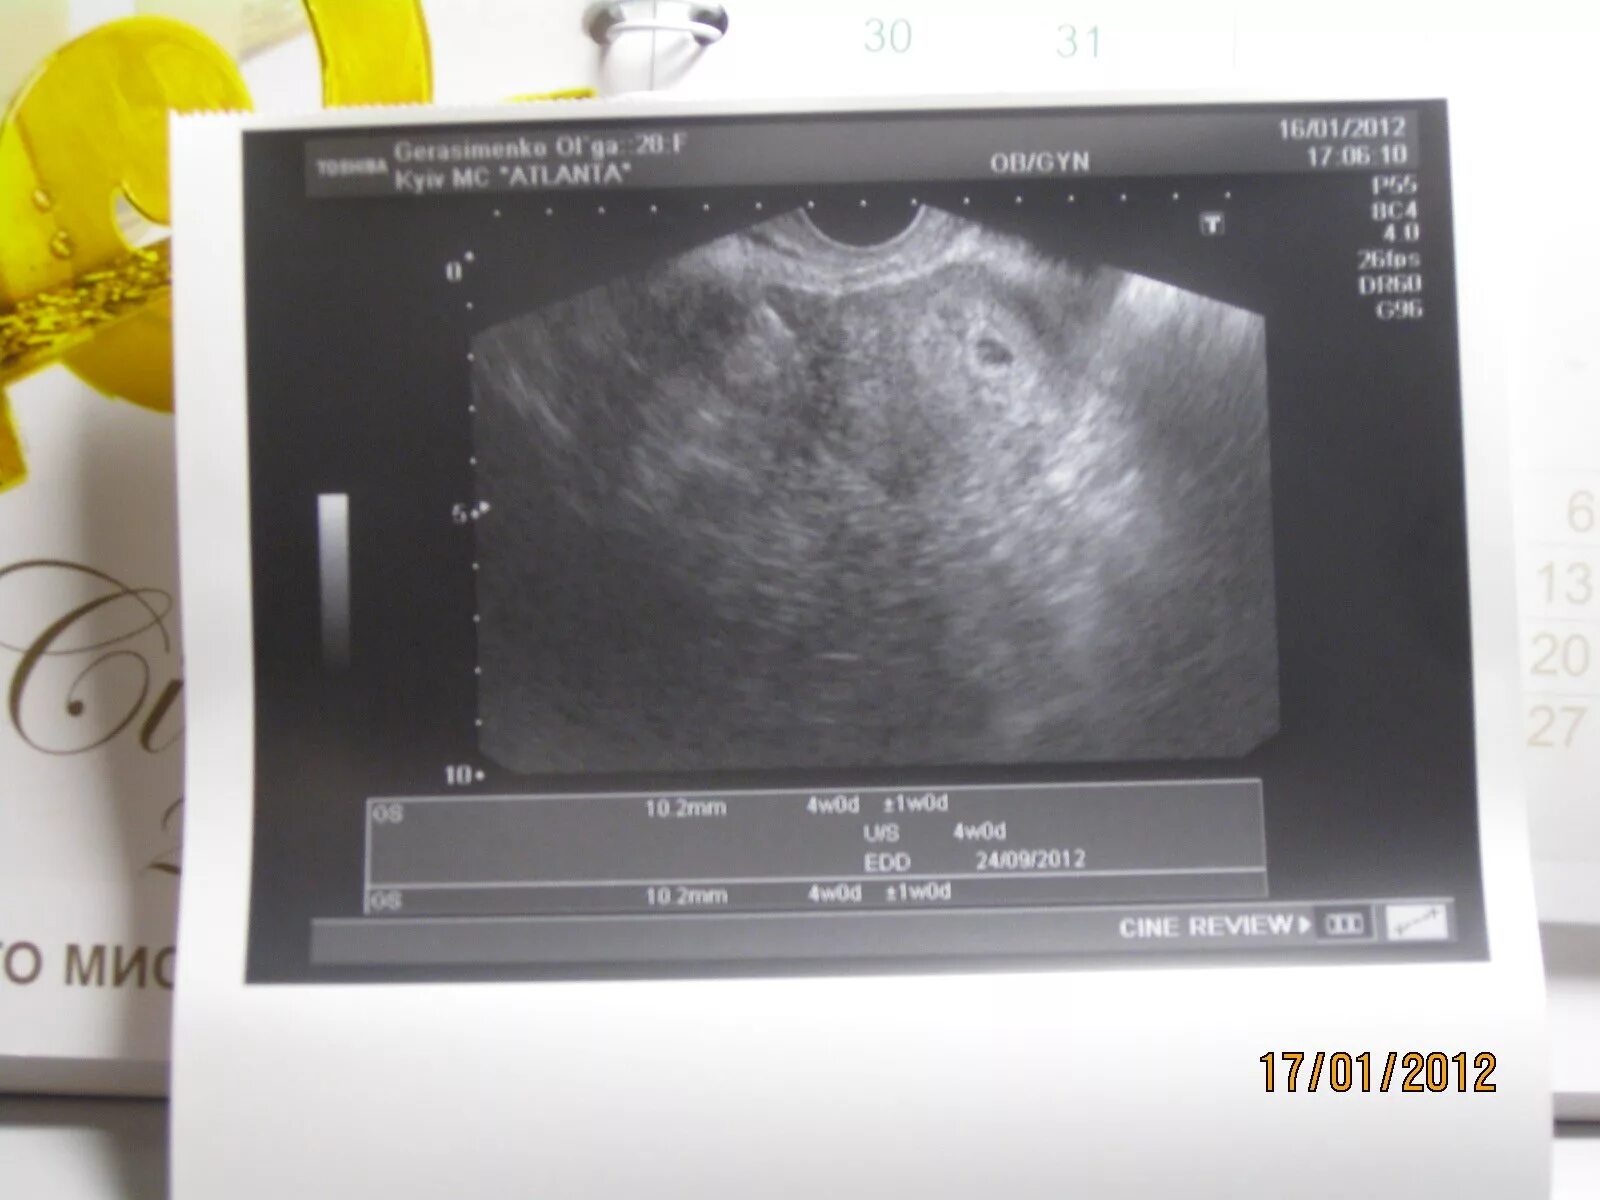

Срок 4 недели 4 дня